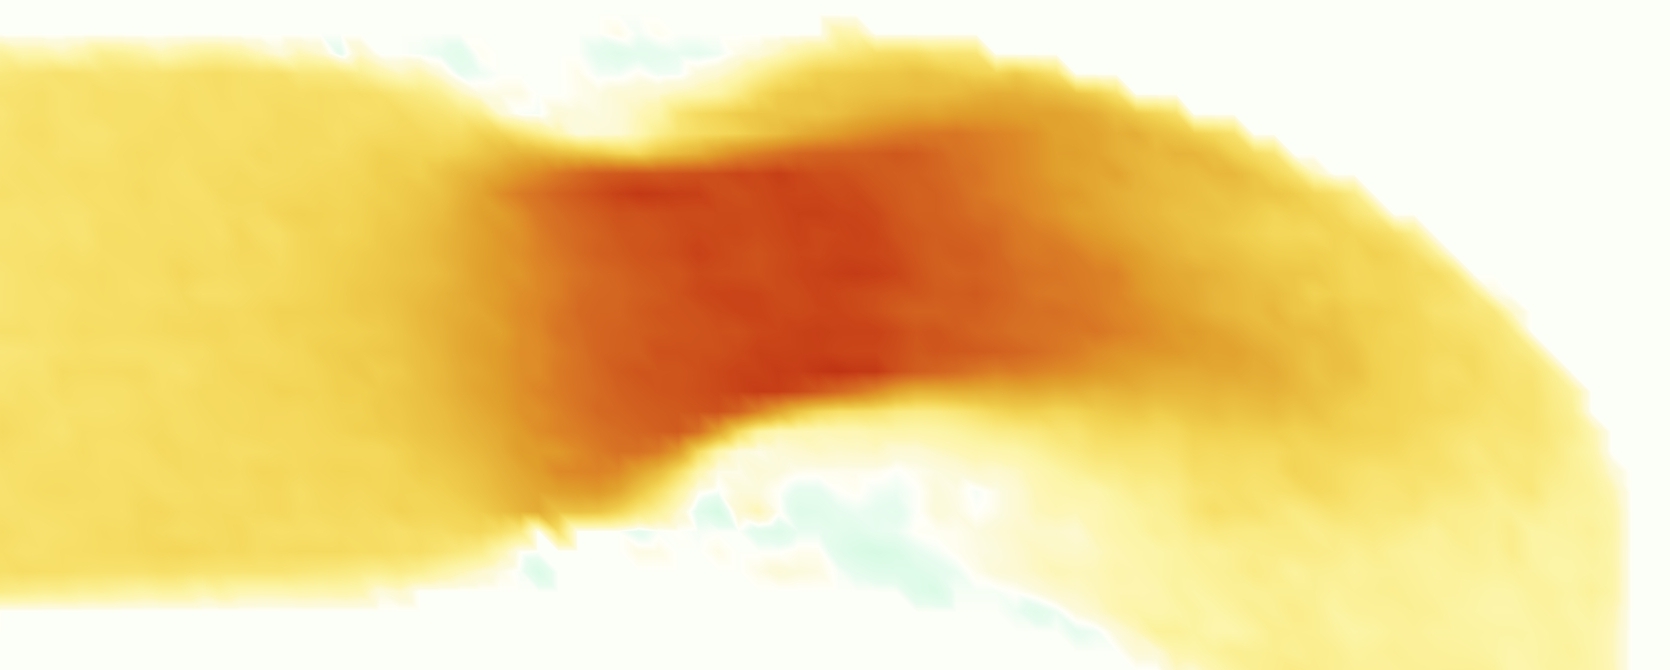

The emergent hemodynamics showed excellent qualitative agreement with experiments. Slice views of the axial component of fluid velocity ( component) in the sagittal plane that cuts through the center of the vessel, parallel to the flow direction, are shown in Figure 5. The flow in both the simulation and the experiment began to accelerate at the same time, with a jet forming through the open valve leaflets. The velocity, angle, and shape of the jet agreed well between the two cases during systole. The simulation captured the slight upward angle of the jet, which was not fully centered in the vessel. It also matched the location where the jet impacts the wall and the slower speed of the jet as it turns with the MPA downstream. As the flow decelerated, the fluid along the interior curve of the vessel reversed first while forward flow persisted where the jet was strongest, as seen in both the simulation and experimental results.

In both the experiment and the simulation, a separation region of reverse flow developed along the interior curve of the vessel under the core jet through the valve. The reverse flow began to develop at the same time in the cardiac cycle and grows throughout systole. The simulation lacked reversed flow in the entire region where reversed flow was present in the experiment, but this region developed some flow separation and had much slower flow than elsewhere in the vessel. Thus, the simulation captured that this is a distinct region from the core jet through the valve opening. There was a smaller amount of slower and slightly reversed flow along the outer curve of the vessel, close to the valve annulus and scaffold support. This region was well-matched between the experiment and the simulation.